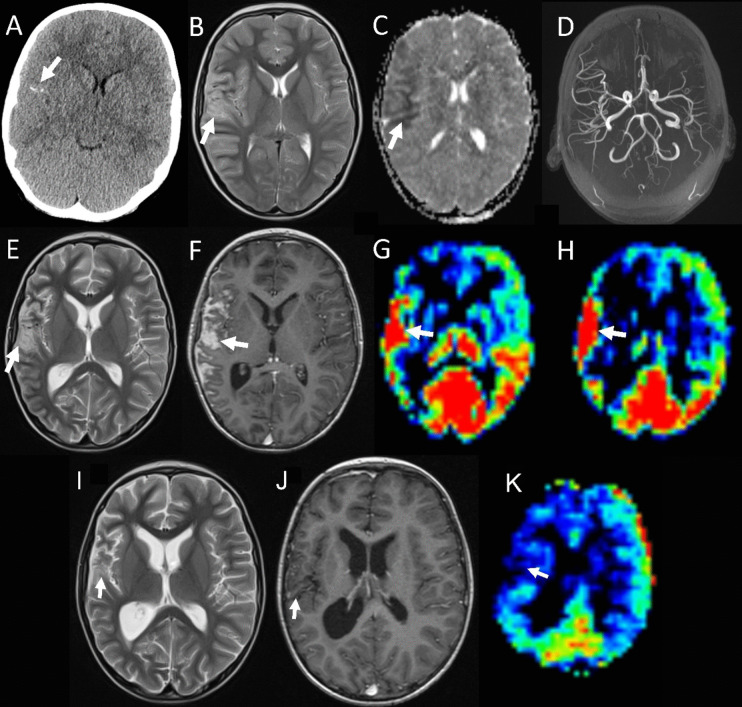

Case presentation: We describe a 7-year-old male presenting with a PDL MYC-subgroup ATRT. The patient received multimodal upfront therapy, including high-dose craniospinal radiotherapy, embedded within a chemotherapy backbone. An unexpected clinical and radiological improvement was also observed upon cessation of all therapy for presumed disease progression. Although the patient eventually succumbed to the disease at 30 months, he demonstrated the longest survival for any PDL ATRT patient reported (median 8 months).

Conclusion: Exhaustive literature review identified seven preceding published cases of PDL ATRT. Ours is the only one to have molecular subgrouping assigned. Perfusion imaging, within a multi-parametric diagnostic package, may be a sensitive marker for malignancy against other aetiologies in challenging presentations. Acknowledging the scarcity of the entity, we cautiously suggest a combination of chemotherapy and upfront high-dose craniospinal radiotherapy, if appropriate, may prolong survival for older children with PDL ATRT compared to exclusive chemotherapy or focal irradiation-based strategies. Our patient's recovery during palliation following a radiological diagnosis of disseminated relapse highlights the importance of confirming disease recurrence by tissue extraction where feasible.